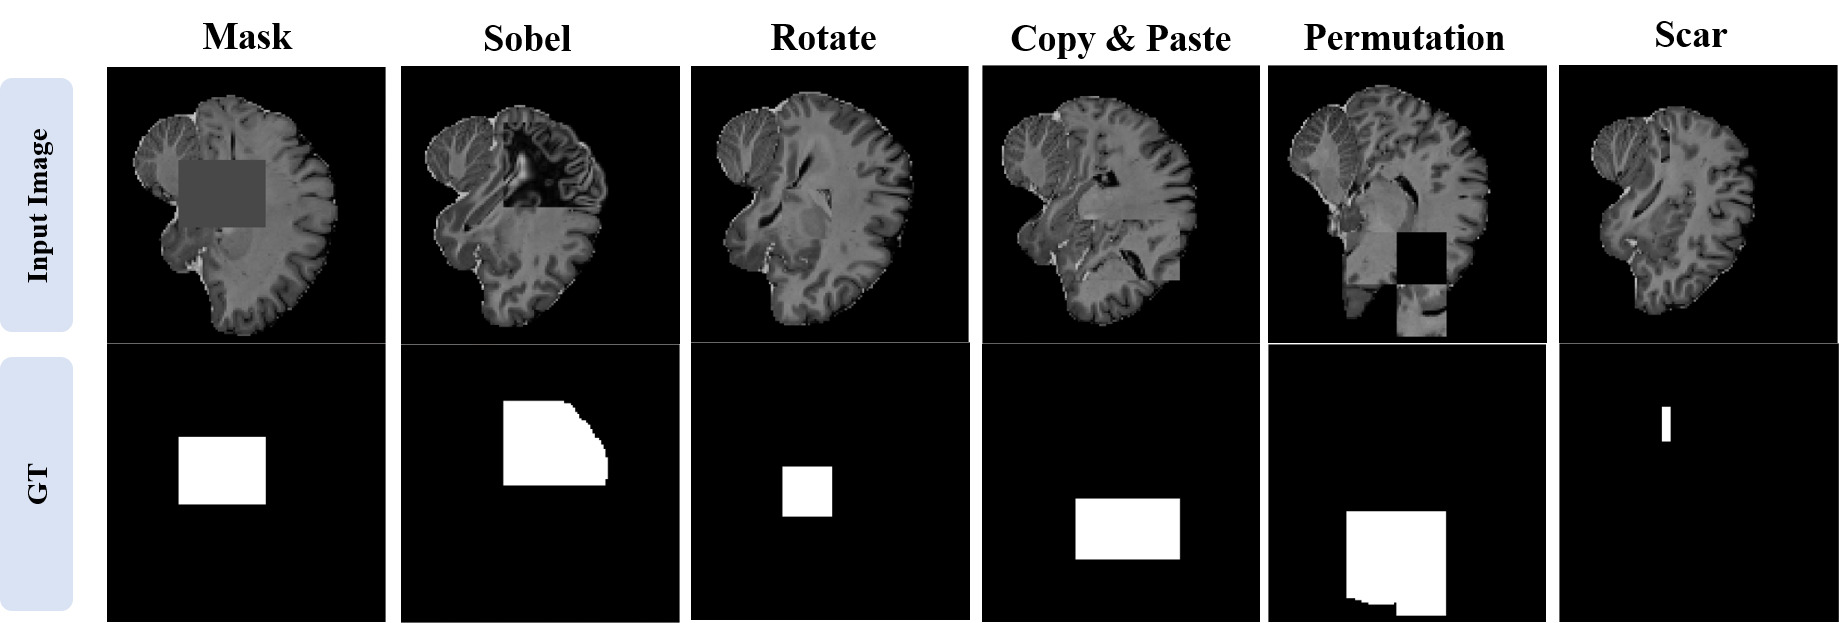

In order to create an reasonable test OOD dataset, we think of various types of augmentation that can be hard augmentation according to the fact that extreme augmentation ruins essential feature of the class [12, 15]. As in Figure 9, there are six types of hard augmentation we have used: mask, Sobel_filter, rotation, Copy-Paste, permutation, and scar. The mask refers to a method of giving a random intensity value , the Sobel_filter refers to a method of applying a Sobel filter to a random patch, and rotation refers to a method of rotating a random patch. The Copy-Paste is a method of pasting a copied patch to another area, the permutation is a method of mixing a random patch with 8 sub-patches divided in the x, y, and z-axis directions, and the scar [27] is a method of applying copy and paste to very small area. Among the parts to which augmentation is applied, if they have the same value as the existing image, the part is excluded from the OOD area. In case of the brain CT image, for example, if the background area is copied and pasted to another background area, this is excluded from the OOD area. During training, both normal and abnormal images for the same image are used as input images to learn features of the normal and the anomaly image simultaneously.

Additionally, we tested on mask test dataset to check robustness to diverse shapes, positions, size and intensities. The mask test dataset have two shapes, twenty seven positions, three sizes, and four intensities of the OOD area.